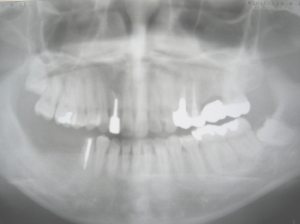

他歯科医院で右下の奥歯を1本抜歯。

前後の歯を削ってかぶせ物。

抜いた部分の歯の負担がかぶせた奥歯にかかり、

歯が割れて痛いと言って当院に来院。

47番が歯根破折

割れて痛い歯を抜歯。

右下にインプラントを植立

2003/10/30の現状